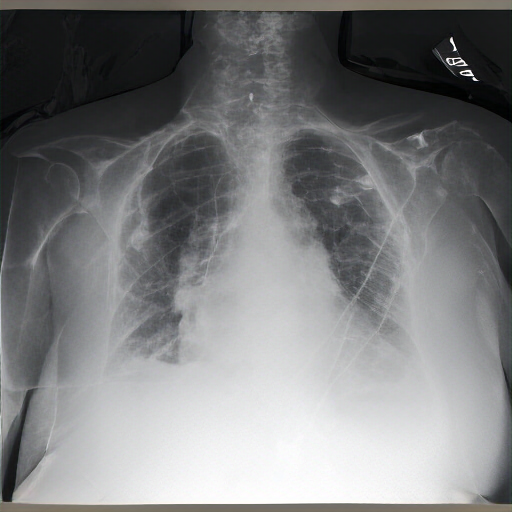

There are moderate-to-severe vascular congestion as well as perihilar opacification on the left than on the right. There is indistinctness of pulmonary vessels, suggestive of small-to-moderate pulmonary edema. There is no pneumomediastinum, a new small-to-moderate right-sided pleural effusion has not changed allowing for somewhat. There is no definite pneumothorax. A dialysis catheter has been removed.

Severe cardiomegaly is present. Previous mediastinal widening has improved. A region of consolidation, more discrete at the right base and in the left lower lobe, presumably with long-standing infection, is noted. There is increased vascular engorgement. No pulmonary edema is seen. Mediastinal vascular engorgement is present. A dual-channel hemodialysis catheter is at the cavoatrial junction, and atrial node tubes are in place.

As compared to the previous radiograph, there is pneumonia in the right upper lobe, better visible on the lateral radiograph and moderately dense on the frontal radiograph, appearing more extensive. A newly appeared retrocardiac lung opacity suggests possible re-expansion by a malignancy. A pre-existing lung opacity in the left retrocardiac region has increased substantially. The opacity is likely large, potentially pneumonia in the lateral location. The opacity is confirmed on both the lateral and frontal radiographs, consistent with the clinical presentation.

The lungs are well expanded and appear clear. Cardiomediastinal silhouette and hilar contours are otherwise unremarkable. No pleural effusion, or pneumonia pneumothorax. IMPRESSION: No acute cardiopulmonary process or evidence of traumatic injury or acute aortic abnormality are. Consider CT to be in etiology and sensitivity for fractures.

Right central venous catheter terminates in the right atrium. No pneumothorax. Overall low lung volumes are stable. Diffuse right paratracheal and pulmonary mass is better assessed on recent prior chest imaging. No underlying consolidation is identified. Retrocardiac opacity represents atelectasis and may also be secondary to patient rotation and low lung volumes. No pleural effusion or pneumothorax. Left-sided lateral airspace opacities persist which may relate to the known effusions. Mediastinal contours are unremarkable.

Frontal and lateral views of the chest are obtained. Relative subtle posterior left base linear opacity, best seen on the lateral view, appears similar to scarring. Aside from minimal linear atelectasis/scarring, no scarring is noted. No focal consolidation. No pleural effusion or pneumothorax. The cardiac silhouette is stable. Left humeral costochondral calcifications are noted. No definite pulmonary edema is seen.

Study is limited due to patient rotation. The heart remains within mild normal limits. Mediastinal contour is stable. The hilar contours are normal. No overt pulmonary edema is demonstrated. Minimal linear opacity within the right lung base is due to subsegmental atelectasis. Low lung volumes are noted with mild elevation of the right hemidiaphragm. No focal consolidation, pleural fluid, or pneumothorax is visualized. Minimal linear opacities in both lung bases are likely atelectasis. Remote right clavicular fracture is noted with associated degenerative changes.

The lungs are hyperinflated, consistent with COPD. No consolidation or pneumothorax. Linear opacities are seen in the right lower lung, likely due to atelectasis. Streaky opacity within the right lung base is again seen without correlate on the frontal view, possibly representing atelectasis or overlying structures of the right lower lobe. No pneumothorax or pleural effusion is detected. The cardiac silhouette is not enlarged, and mediastinal contours appear within normal limits.

Patient is status post median sternotomy and aortic valve repair. Cardiac, mediastinal, and hilar contours are stable. Pulmonary vasculature is not substantially changed from the previous interval. Linear opacities within the left lung base may reflect areas of subsegmental atelectasis. Patchy opacities in the lung bases appear increased with areas of atelectasis. No pneumothorax is demonstrated. Bilateral hilar changes may likely be chronic. The aortic knob is calcified.

PA and lateral chest radiographs demonstrate hyperinflated lungs, suggestive of COPD. Otherwise, there is no focal consolidation, pleural effusion, or pneumothorax. The cardiomediastinal and hilar contours are normal. No acute osseous abnormalities are detected. No acute cardiopulmonary abnormality is present. Postsurgical changes are noted in the upper abdomen.

FINDINGS: The lungs are hyperinflated but without focal consolidation. No pleural effusion or pneumothorax is seen. The cardiac and mediastinal silhouettes are unremarkable. No pulmonary edema is seen. Bilateral hila are unremarkable. IMPRESSION: Lungs remain hyperinflated, suggesting possible COPD. No focal consolidation is seen.

The image is a radiograph of the chest, showing the thoracic cavity structures. Multibibasilar opacities could represent overlap of the apex. No clinical evidence for pneumonia. There are new bilateral infrahilar infiltrates and mild pulmonary edema with flattening of the diaphragmatic contour.